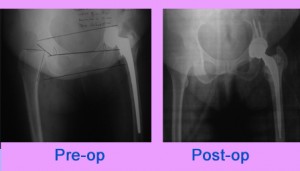

63 yrs old lady presented to us with complains of pain around Left hip with difficulty in walking. She is a operated case of bipolar Talwalkar prosthesis for fracture neck of femur done 4 years back. Radiographs shows protrusio of the implant .

Implant removal and revision Total Hip Replacement was ... Read more..